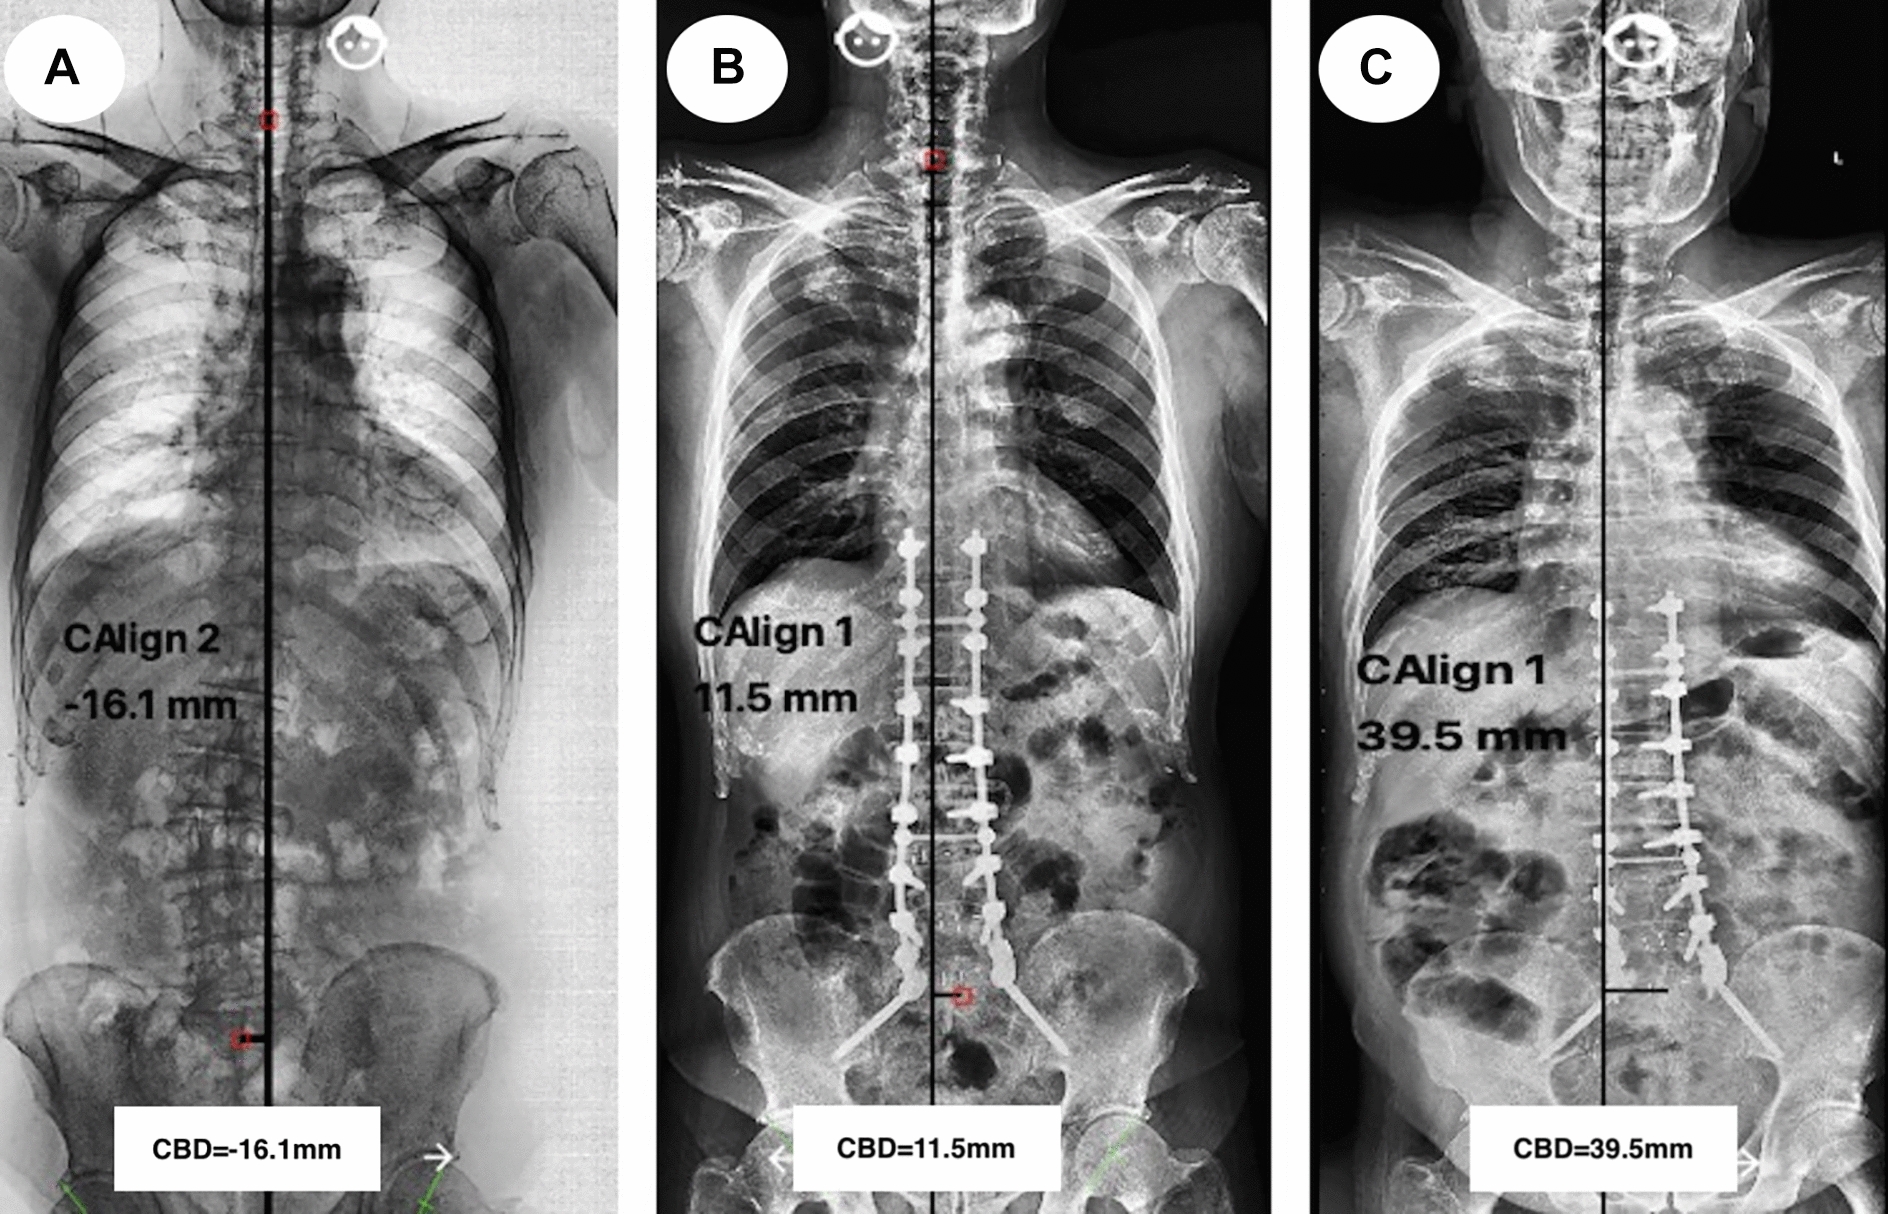

Thomapson et al. [ref. 21] insisted that the incidence of CM postoperatively could be reduced by avoiding overcorrection in coronal deformity for patients who had undergone long-fusion surgeries with instrumentations. In our current study, CM-free survival time decreased significantly in patients with CBD correction increasing after Kaplan–Meier survival analyzing. Moreover, over correction of CBD (≥ 30 mm) were the risk factors for CM-happening during follow-up according to the multivariate analysis via a Cox proportional hazards model. A male patient with ASD underwent long-fusion surgery (T10–S2) in Fig. 5 showed that CBD was corrected from − 16.1 mm preoperatively (Fig. 5A) to 15.5 mm immediate postoperatively (Fig. 5B), and the CBD increased up to 39.5 mm (Fig. 5C) at the final follow-up. Moreover, the pelvic fixation and instrumented vertebras over 8 in this patient may increase the incidence of CM-developing during follow-up.